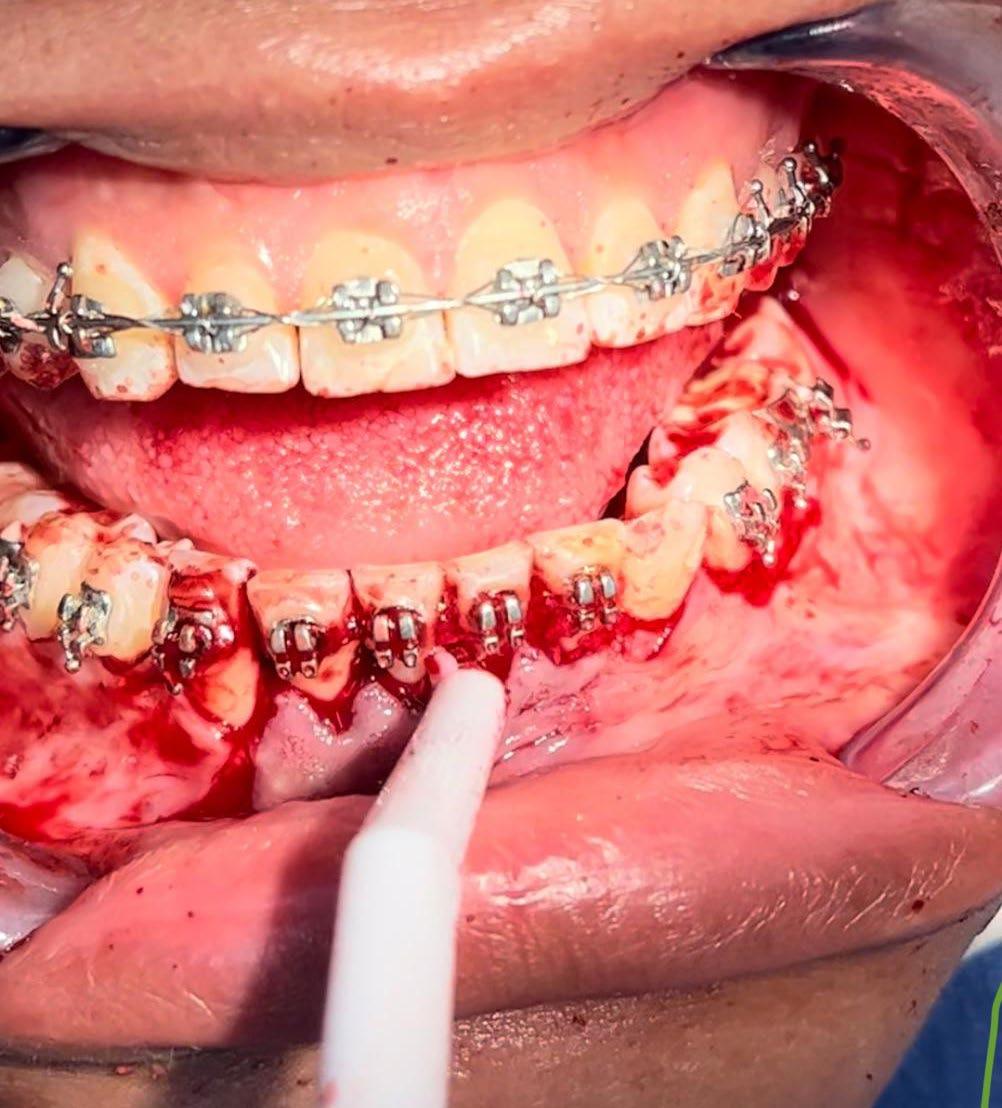

El tratamiento se realizó en las siguientes fases: la fase prequirúrgica incluyó la alineación, nivelación y la

extracción de los segundos premolares superiores e inferiores, con cierre de espacios. En la fase quirúrgica, se realizó una mentoplastia de avance e implantes en la zona malar. La fase postquirúrgica consistió en el detallado-retención. La aparatología utilizada fueron brackets de prescripción Roth .022 × .028; se colocaron bandas en los primeros molares superiores e inferiores, con tubos punteables en los O.D. 16, 26, 36 y 46, y tubos bondeables en el O.D. 27, además de un arco transpalatino y un arco lingual.

El tratamiento se realizó en las siguientes fases: la fase prequirúrgica incluyó la alineación, nivelación y la extracción de los segundos premolares superiores e inferiores, con cierre de espacios.

Previa asepsia y antisepsia, más colocación de campos en forma habitual, mediante infiltración troncular y de forma local, se realiza incisión

marginal con descarga lineal para levantar un colgajo seminewman (Figura 3). Se realiza ostectomía y osteotomía para liberar el órgano dentario retenido y facilitar su extracción (Figura 4). Una vez fuera de la cavidad bucal, se realiza tratamiento de conductos y obturación. De forma simultánea, se lleva a cabo la extracción atraumática del órgano dentario 73 (Figura 5) y la preparación alveolar del lecho receptor para recibir el órgano dentario a trasplantar bajo parámetros quirúrgicos (Figura 6).

Se enfatiza la mínima manipulación de los tercios radiculares del órgano dentario a trasplantar, intentando preservar, en lo posible, las fibras del ligamento periodontal. Se mantienen condiciones de hidratación a base de agua bidestilada durante su preparación, así como la sustitución neurovascular en su forma extrabucal. A nivel de los lechos receptores, se sigue un protocolo bacteriostático y bactericida no quelante.

En la zona postextracción del canino retenido (Figura 7), se realiza la conformación con materiales biocompatibles a base de xenoinjerto bovino y membrana de colágeno, para favorecer la correcta reparación de los tejidos blandos y duros, dadas las dimensiones del probable defecto, finalizando con sutura absorbible Vicryl 3-0 (Figuras 8 y 9).

se coloca en la correcta posición infraerupcional, verificando la ausencia de puntos altos de contacto y considerando la armonización dentooclusal (Figura 10).

Se coloca una férula a base de resina epóxica, estabilizándola al arco utilizado en el tratamiento de ortodoncia que conforma la arcada mandibular. Asimismo, se coloca una guarda a base de acetato rígido no. 35, liberando al órgano trasplantado de un posible trauma oclusal (Figura 11).